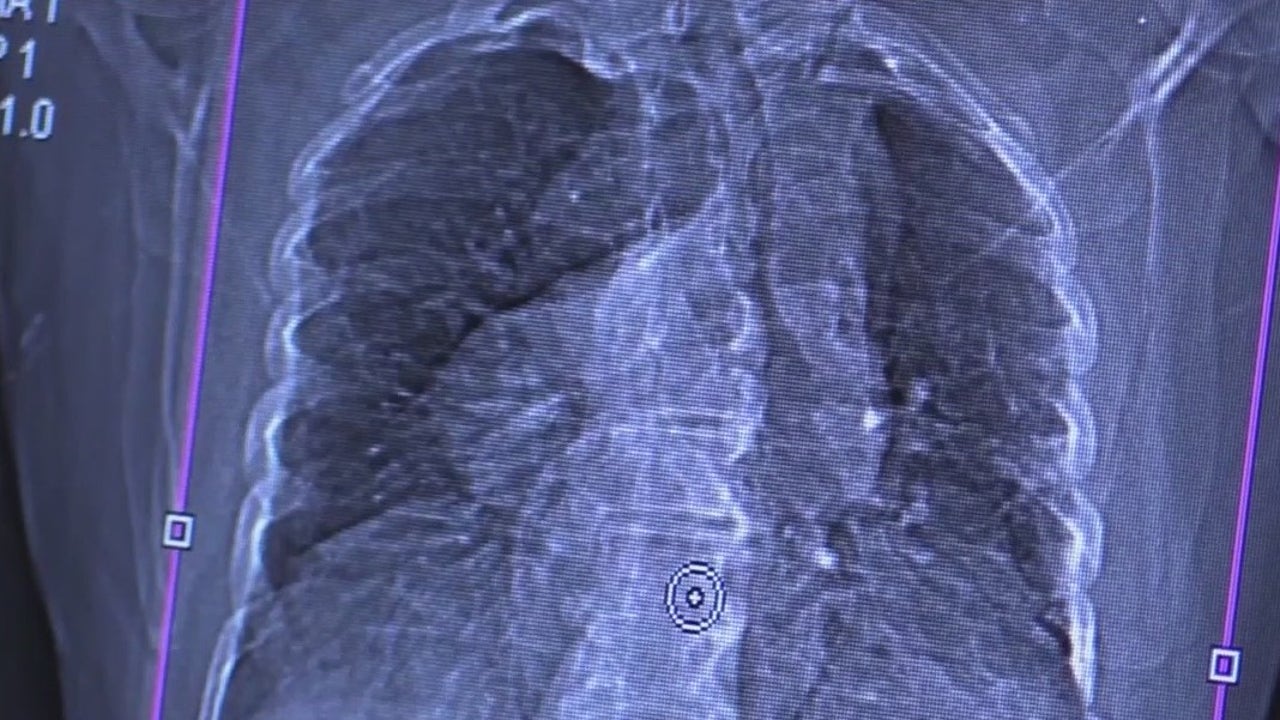

ORLANDO, Fla. - Kristen Kowall was diagnosed with COVID-19 in June 2020. Ashley Hoven was diagnosed in October 2020. Both are still feeling the effects. They are COVID long-haulers.